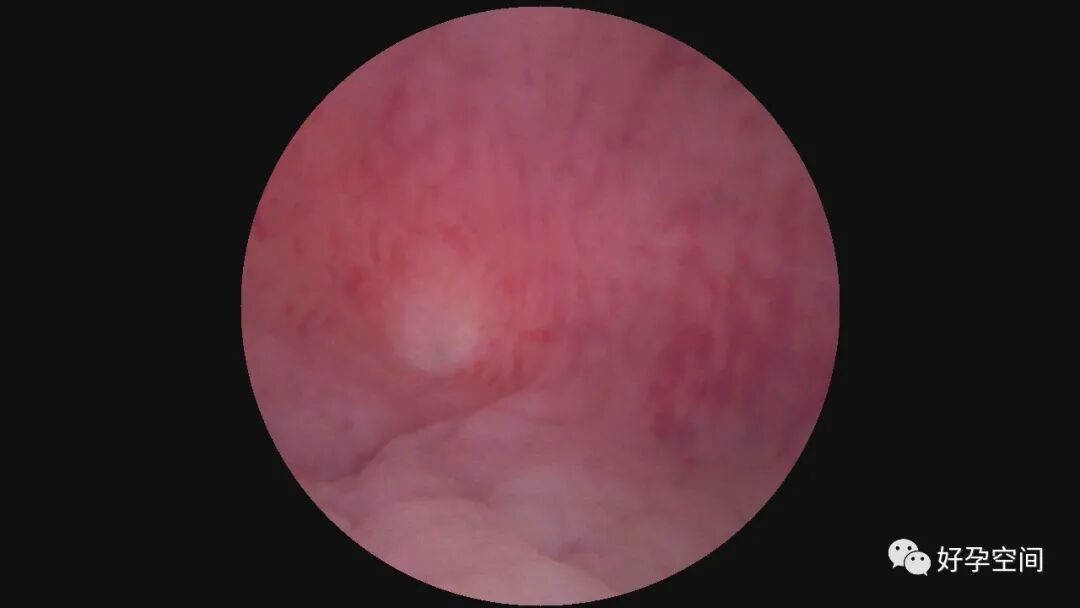

病例3:30岁,G3P1,顺产1次,孕12周胚胎停育1次并清宫,本次停经9+周,稽留流产。一次性宫腔镜见宫颈管下段息肉,约2.0*1.0*0.8cm,胚胎着床于宫腔下段后壁,不规则,张力差,摘除胚胎、切除息肉后见宫腔左侧粘连,切除粘连,宫腔形态正常,双侧输卵管开口可见。

病例4:30岁,G2P1,剖宫产1次。本次停经40+天,计划外妊娠。一次性宫腔镜见胚胎着床于宫腔左后壁,约3cm*3cm*2.5cm,摘除胚胎后宫腔形态正常,双侧输卵管开口可见。